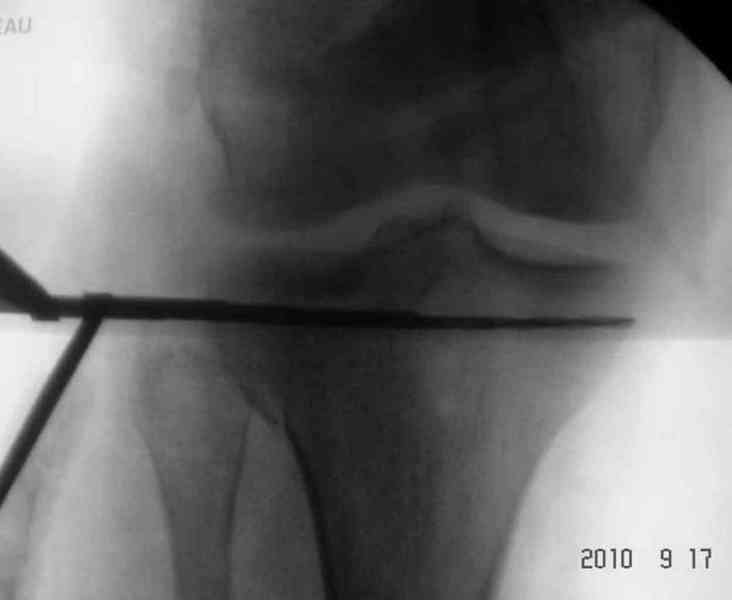

В остром периоде для стабилизации перелома подойдет любой дистракционный аппарат "голень-стопа", и больной получит свободу от скелетного вытяжения.

Больному 46 лет, активный, молодой, и не стоит так долго держать на вытяжении. Тем более, АВФ комфортабельнее, лучше переносят, а при односторонних повреждениях больные могут передвигаться с помощью костылей без посторонней помощи.

Мы применяем обычные стержневые аппараты, но у кольцевых свои имущества, их в нужный момент с помощью дополнительных колец или спиц можно превратить в постоянный.

У больного двухстороннее повреждение, ограничен в нагрузке не менее 8-10 недель. После односторонней фиксации будет активным, хотя бы в пределах койки. Без спешки дождаться улучшения кожных покровов, и аппаратом Илизарова в комбинации с шурупами или спицами, из мини-доступов.